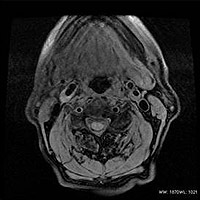

AIR Recon DL画像の一例

脳

頚動脈プラーク